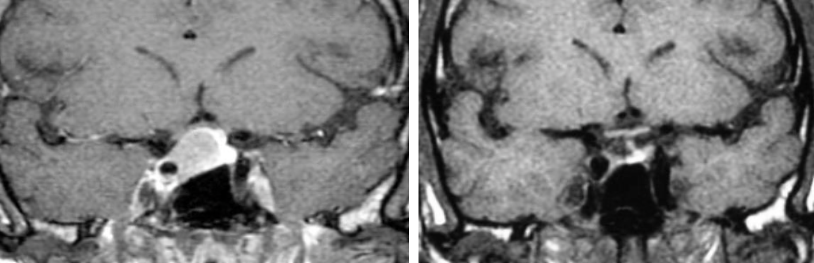

MRI Pituitary pre and post-surgery